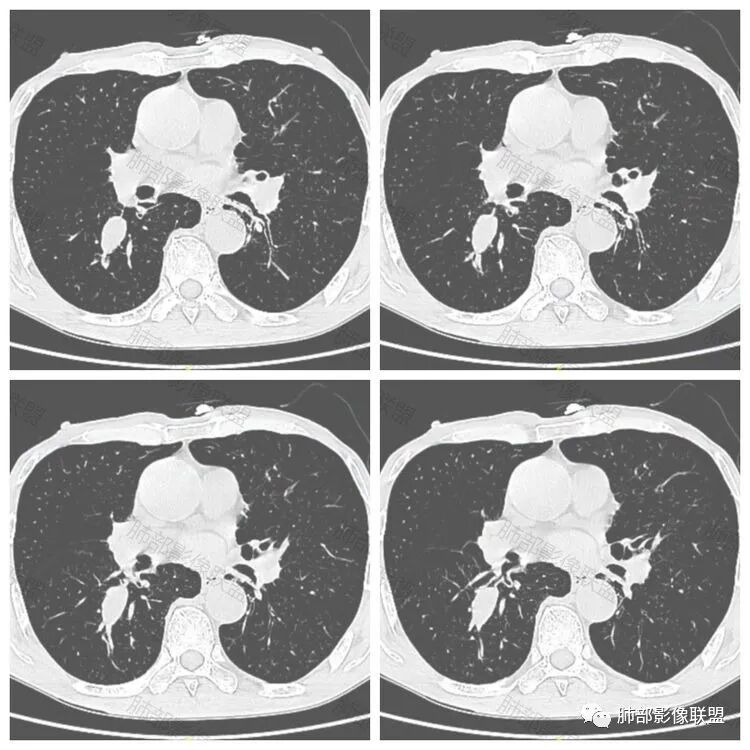

老年男性患者,胸部隐痛1月入院,有长期吸烟史,胸部CT:右肺下叶背段梭型结节灶,边界清晰,无明显分叶、毛刺及周边磨玻璃影,内部密度不均匀,支气管截断,增强扫描不均匀轻度强化,内部似乎见支气管黏液栓,纵隔淋巴结不大,考虑恶性病变:小细胞癌(缺少典型的纵隔肺门淋巴结增大融合),鳞癌(病史复合,但没有阻塞性肺炎,内部没有坏死,),类癌(多见于女性患者,与吸烟关系不大),首先考虑典型类癌,

老年男性,右肺下叶梭形或椭圆形结节,形态较规则,边缘光整,支气管截断,增强不均匀轻度强化,右肺门及纵隔淋巴结增大,考虑恶性病变,鳞癌或小细胞癌,神经内分泌癌(小细胞形)。

老年男性患者,右肺下叶背段梭形结节影,边界比较光整,密度均匀,没有明显的分叶毛刺,没有阻塞性肺炎的表现,这些感觉具备有良性的特点。而近端支气管截断,增强明显的强化,纵隔多发的淋巴结,显得是恶性的特点。总体印象,老年患者+支气管截断征象+明显强化的结节+纵隔多发淋巴结,还是考虑恶性结节,小细胞癌或是鳞癌。

男性,老年人,长期吸烟史,老慢支背景,右下肺背段占位,支气管亚段门口堵,病灶长轴与支气管平行,推测腔内生长可能,病灶内血管穿行,周围干净,轻度强化,右肺门淋巴结肿大,考虑恶性,神经内分泌癌(大小类)>淋巴上皮瘤样癌>腺癌>鳞癌

右肺下叶梭形实性结节,密度均匀,边缘光整,局部膨隆,近端支气管截断,轻度强化,血管走行自然,右肺门及纵隔淋巴结增大,考虑小细胞癌>鳞癌

右肺下叶背段结节,沿着支气管走行呈长椭圆形,边缘圆滑清晰,近端支气管阻塞,远端支气管有沿壁增厚,右肺门淋巴结肿大,中度强化,老年男性,吸烟病史,肺气肿背景,考虑小细胞肺癌,鉴别鳞癌

老年男性,吸烟史,右肺下叶梭形肿块,边缘平直有分叶,支气管近端阻塞,右肺门肿大淋巴结,增强后轻度强化,欠均匀,首先考虑恶性,小细胞肺癌?

老年男性+吸烟+右下肺肿块影+支气管截断+淋巴结肿大,考虑恶性,倾向小

老年男性,吸烟史,右肺下叶背段梭型软组织肿块,边缘膨隆,不均匀强化,近端支气管截断,同侧肺门及纵隔淋巴结肿大,支持恶性,小细胞可能大,鳞癌缺少阻塞性改变

晨读,右下叶梭形占位,边界光滑,支气管截断,可见尾征,不均匀轻度强化,肺门淋巴结肿大,有吸烟史,高龄高危患者,首先考虑恶性,考虑小细胞癌,鉴别一下鳞癌

老年男性,前胸隐痛1月。2年前有白内障手术史。右下肺结节,沿中轴呈梭形,膨隆,边清、无分叶,无毛刺,近端支气管截断完全堵塞,病灶以远未见阻塞性炎症及肺不张。内部密度基本均匀,增强轻微强化,似见局部低密度影。纵隔及右肺门见肿大淋巴结。整体考虑恶性可能性大,小细胞癌?鳞癌?注意鉴别良性结节—错构瘤。

老年男性,长期吸烟史,右肺下叶背段梭形低密度灶,边界清晰,无明显分叶、毛刺,边缘稍彭隆,支气管截断,右肺门淋巴结增大,增强扫描不均匀轻度强化(延迟略明显),首先考虑恶性,小?不典型结核球待排。

右肺下叶背段结节,气管堵塞,密度均匀,边界清晰,无明显分叶、毛刺,边缘膨隆,右肺门淋巴结增大,增强轻度强化,考虑小细胞癌,鉴别鳞癌。

右肺下叶梭形软组织结节,密度均匀,明显尾巴,边缘光整,近端支气管截断,轻度强化,血管走行自然,又腊肠尾巴征象

考虑恶性  小细胞癌?

男,83,前胸部隐痛不适1月。有长年大量吸烟史。胸部CT:肺气肿,右肺下叶纺锤型实性结节灶,边界清晰,支气管截断,内部密度不均匀,增强扫描不均匀强化,右肺门淋巴结大。考虑恶性病变:小?鳞?鉴别炎性肉芽肿、错构瘤等。

晨读:老年男性+吸烟+右肺下叶与气管长轴一致的梭形肿块影+支气管截断,轻度强化,右肺门肿大淋巴结,考虑恶性,小细胞肺癌可能,鉴别鳞癌

呈典型管状改变,近端支气管堵塞、稍扩张,病灶有强化倾向于恶性,没有强化倾向于炎性病变(结核之类);近端呈结节状(鳞癌多一些),这个病例呈管状(小细胞Ca多一些);平扫与强化有差异,有轻度强化,是粘液栓还是血管?